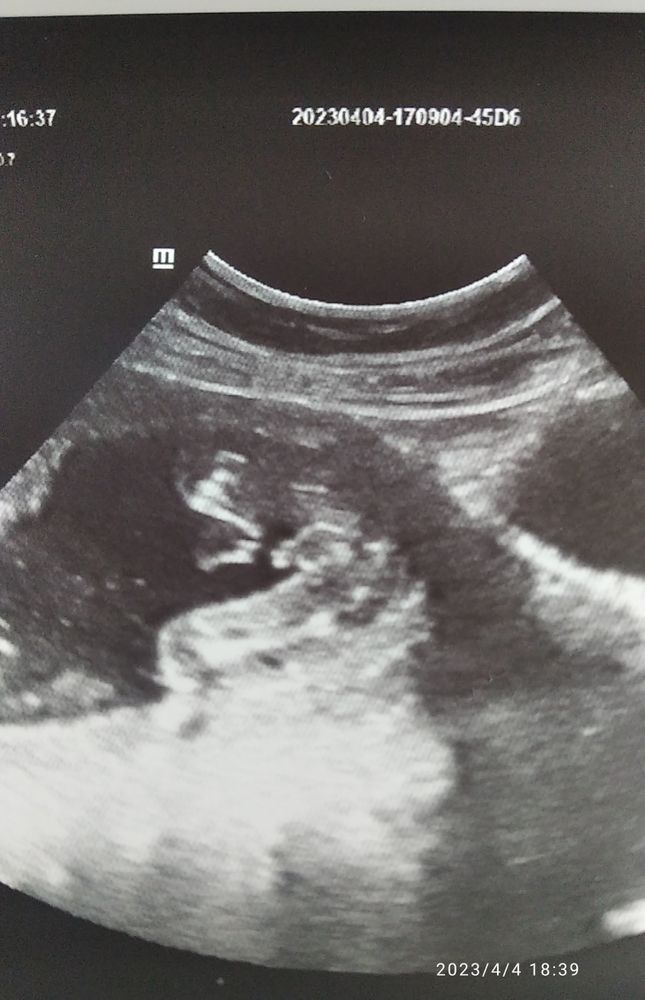

Пол ребенка

Что тут определять 😂 мальчик🥰 чихните и на меня мамочка 😊

Вы сами яички то не видите ?😀очевидно же

Катя, я вижу 😊, но врач на УЗИ не смогла определить пол малыша.,🙈Хотелось уточнить на сайте 🙂 Что не одна я вижу мальчика.🤣

Anna SPB, вот к сожалению специалист такой попался... 🙈🙈🙈 Специально пошла чтоб пол уточнить, мне на первом скрининге предположили мальчика.Но это было на сроке 12,5 недель.

Так видно же что мальчик невооруженным взглядом

Мужик ясное дело.😀С таким то «хозяйством».

Светлана Сопчинская, спасибо 🙏Сегодня сходила на УЗИ, врач засомневалась и не стала говорить кто у нас.Ничего против не имею,но врач далеко не молодая была.